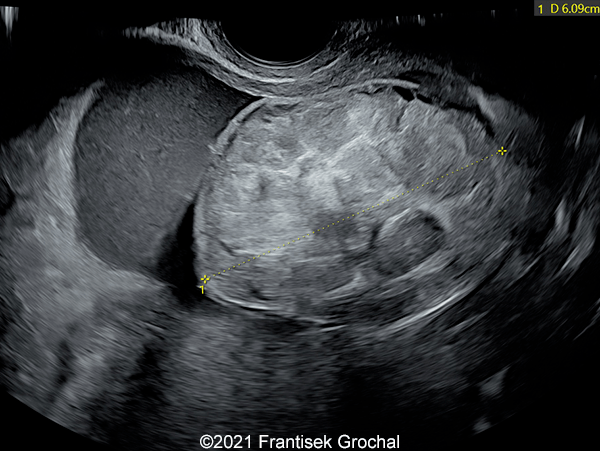

Case Report: A 24-year-old secundigravida, primipara presented to our office at 24 weeks and 6 days of her pregnancy due to a right-sided cranial parieto-occipital mass of the fetus. We obtained the following images.

Our ultrasound images at 24 weeks, 6 days show a highly vascularized, mostly solid mass measuring 58 x 45 x 34mm in the right-parieto-occipital subcutaneous region. Vascular supply of the lesion could be traced to the right vertebral artery. Repeat ultrasound exams done later in pregnancy demonstrated that the size of the mass remained stable with overall mass volume about 58 cm³.